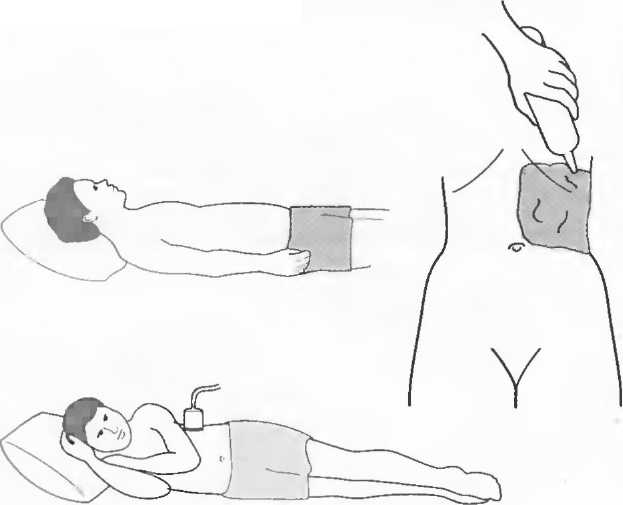

Подготовка

1. Подготовка